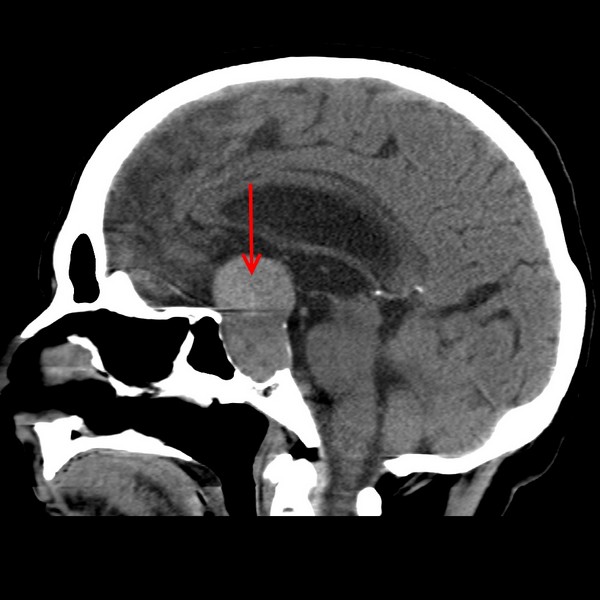

Розміри турецького сідла повинні бути приблизні рівні гіпофізу та допустиме відхилення 1 мм. Середня відстань між задньою і передньою стіною зазвичай становить від 1 до 1,5 см, а від дна порожнини до діафрагми 0,7-1,3 см. Побачити наочно пусте турецьке сідло можна на цій картинці:

Для постановки діагнозу СПТС лікар використовує інструментальні методи обстеження, наприклад, МРТ і КТ. На знімку буде видно будь-патологічні зміни в тканинах головного мозку, в тому числі і в гіпофізі.